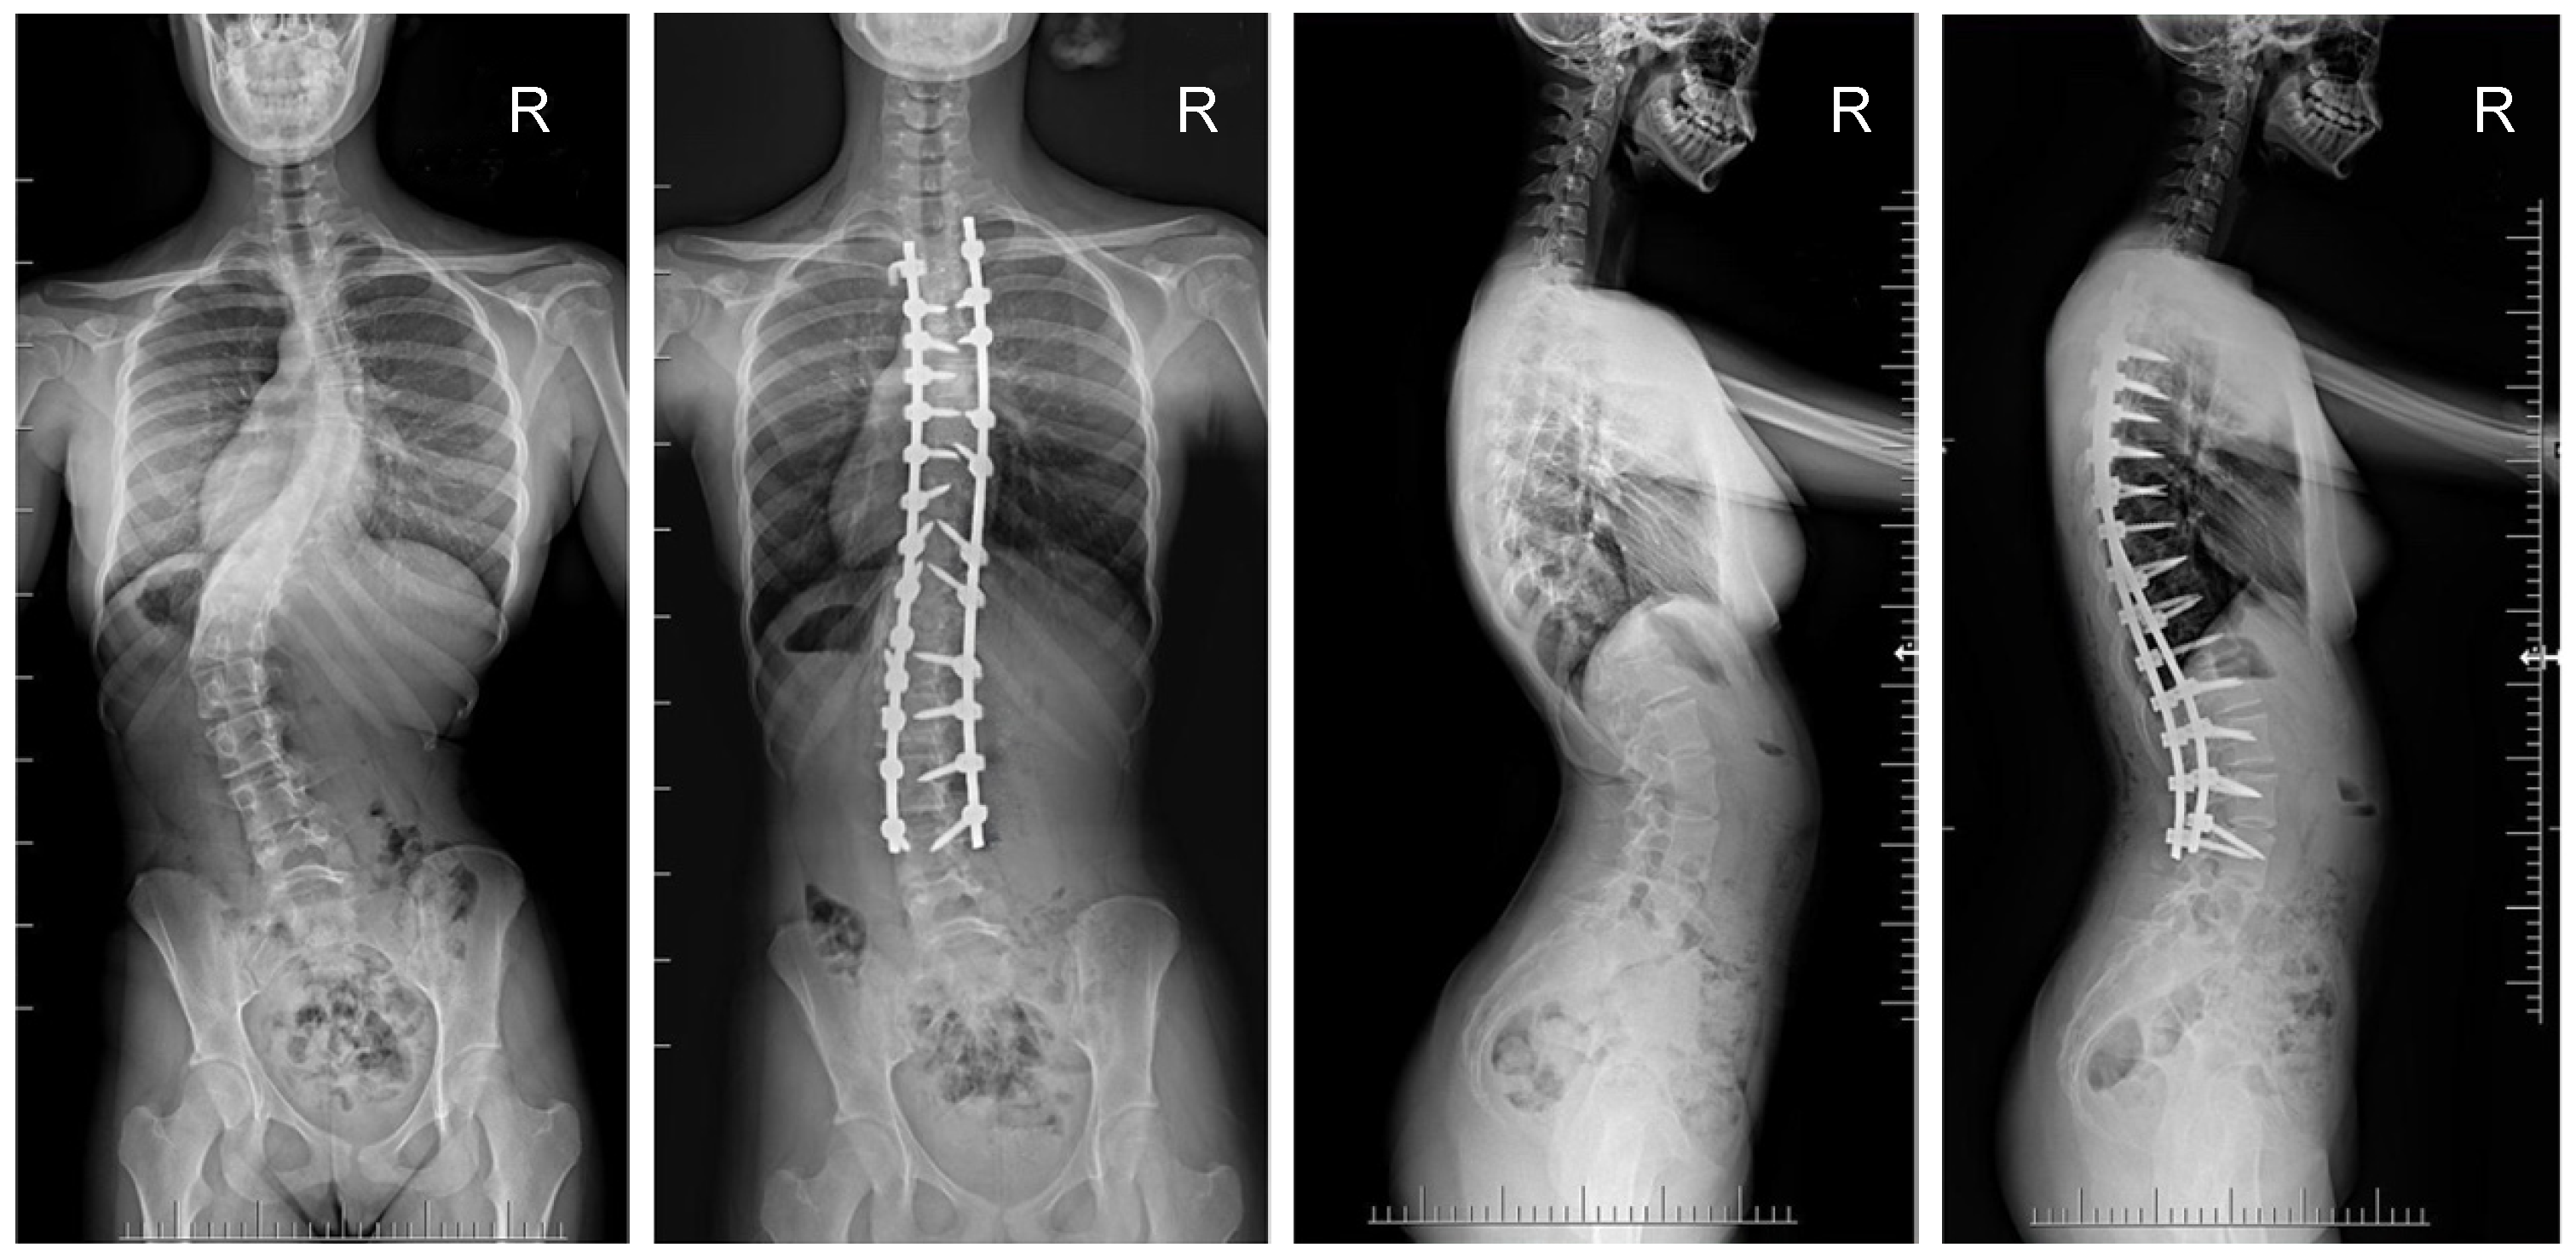

The mean (SD) operative times were recorded as 252 (62.4) minutes for the G1 patients and 344 (82.8) min for the patients in G2. The mean (SD) estimated blood loss levels were noted as 480 (288) mL for the patients in G1 and 632 (278) mL for G2. During statistical analysis, we found no statistically significant differences in either operative time or estimated blood loss between the study groups. The mean (SD) fusion levels were 10.2 (2.8) for G1, and 9.8 (3.2) for G2 (N.S.). The mean (SD) screw densities were noted as 75% (12) for the G1 group, and 75 (10) for the G2 group (N.S.). All analyzed data are presented in Table 1. Figure 1, Figure 2, Figure 3 and Figure 4 show X-rays of exemplary patients with idiopathic scoliosis after surgical treatment from G1 and G2.

Figure 1.

X-rays of an 18-year-old girl with AIS, treated with selective thoracic fusion. A larger screw size of 6.5 mm and 2 cobalt–chromium rods of 6.0 mm were used (G2). X-rays show curve before surgery and correction after surgical treatment.

The correction of spinal deformities using modern systems based on the CD technique enriched with osteotomy techniques of the posterior column of the spine provides powerful opportunities for the correction and stabilization of curvatures [4,8,10,11,12,13]. Many details of implants have evolved and been improved, such as the implant profile, screw head stiffness, mobility in the sagittal axis, and its multi-axial nature, to obtain the best possible correction results [20,21,37,38]. The quality of the rod used is important in three-plane correction, i.e., the metal alloy (titanium, cobalt–chrome) and its diameter, which affects its ability to reproduce the sagittal and frontal balance of the spine [17,18,19,20,21]. It is known from other biomechanical studies that the larger the screw diameter, the better the stabilization and the lower the risk of screw removal and implant loosening [20,23,39,40,41]. For the surgical treatment of AIS, we received excellent outcomes using a system based on CD instrumentation in terms of three-dimensional correction of the spine (Figure 1, Figure 2, Figure 3 and Figure 4 show X-rays of exemplary patients with idiopathic scoliosis after surgical treatment from G1 and G2), the coronal and sagittal planes, derotation, and the clinical outcomes [11,12,13]. It should be emphasized that the correction possibilities of spinal deformation are influenced by other factors that we did not analyze, such as bone quality, so we focused on assessing the results of surgical treatment based on the sizes of the screws and rods used [39,40,41]. Also, the flexibility of the spine assessed on bending films is the main factor influencing the achievement of correction, as well as the loss of correction [42].